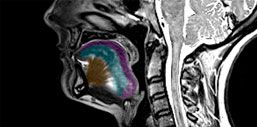

Заболевания моторных нейронов можно диагностировать с помощью МРТ языка